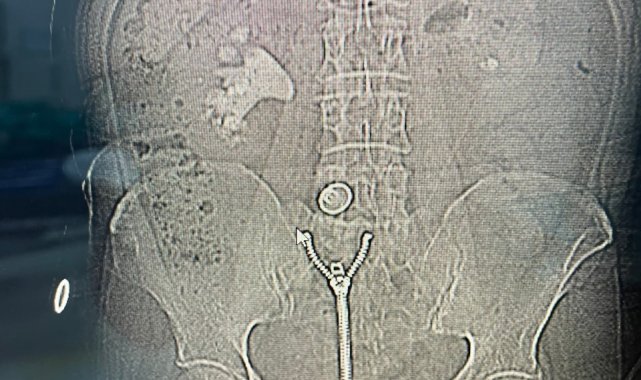

Operasyonu gerçekleştiren Üroloji Kliniği Uzmanı Dr. Mehmet Levent Akbulut, taşın büyüklüğüne dikkat çekerek, "Hastamızın böbreğinde yaklaşık 8 santimetre çapında büyük bir taş vardı. Tıpta bu tabloya 'staghorn', yani geyik boynuzu taşı diyoruz. Eğer bu taş alınmasaydı, böbrek fonksiyonunu tamamen kaybedebilirdi. Biz de perkütan nefrolitotomi adını verdiğimiz kapalı yöntemi tercih ettik. Tomografi yardımıyla planlama yaparak, böbreğe küçük bir delikten girip taşı parçalara ayırarak tamamen temizledik. Ameliyat sonrası hastamızın böbreği taşsız hale getirildi" dedi. Dr. Akbulut, söz konusu yöntemin açık ameliyata göre çok daha hızlı iyileşme süreci sağladığını ve bu tür kompleks operasyonların Malatya'da başarıyla gerçekleştirilebildiğini belirtti.